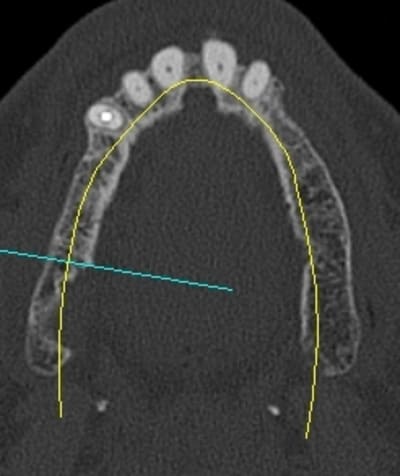

le sujet tombe à pic!

je viens de faire un sinus lift ce matin;

- 3 à 4 mm de hauteur sous sinusienne

- des cloisons de refend partout

- comblement avec du Vital Os

- un implant Axiom D4 L 10

comme je n'avais pas le temps de faire des photos la dernière fois et que j'en étais frustré, je me suis un peu lâcher aujourd'hui...

en ce qui concerne la planification j'ai une 3D kodak je me sert des cotes de l'implant Alphatech qui bien que n'ayant pas la même forme, a les mêmes dimensions.